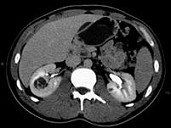

- 单项选择题男,45岁, 右腰部隐痛不适伴无痛性肉眼血尿1月,结合所示图像, 最可能的诊断是 ( )

A、右肾癌

B、右肾血管平滑肌脂肪瘤

C、右肾感染性囊肿

D、右肾盂癌

E、右肾脓肿